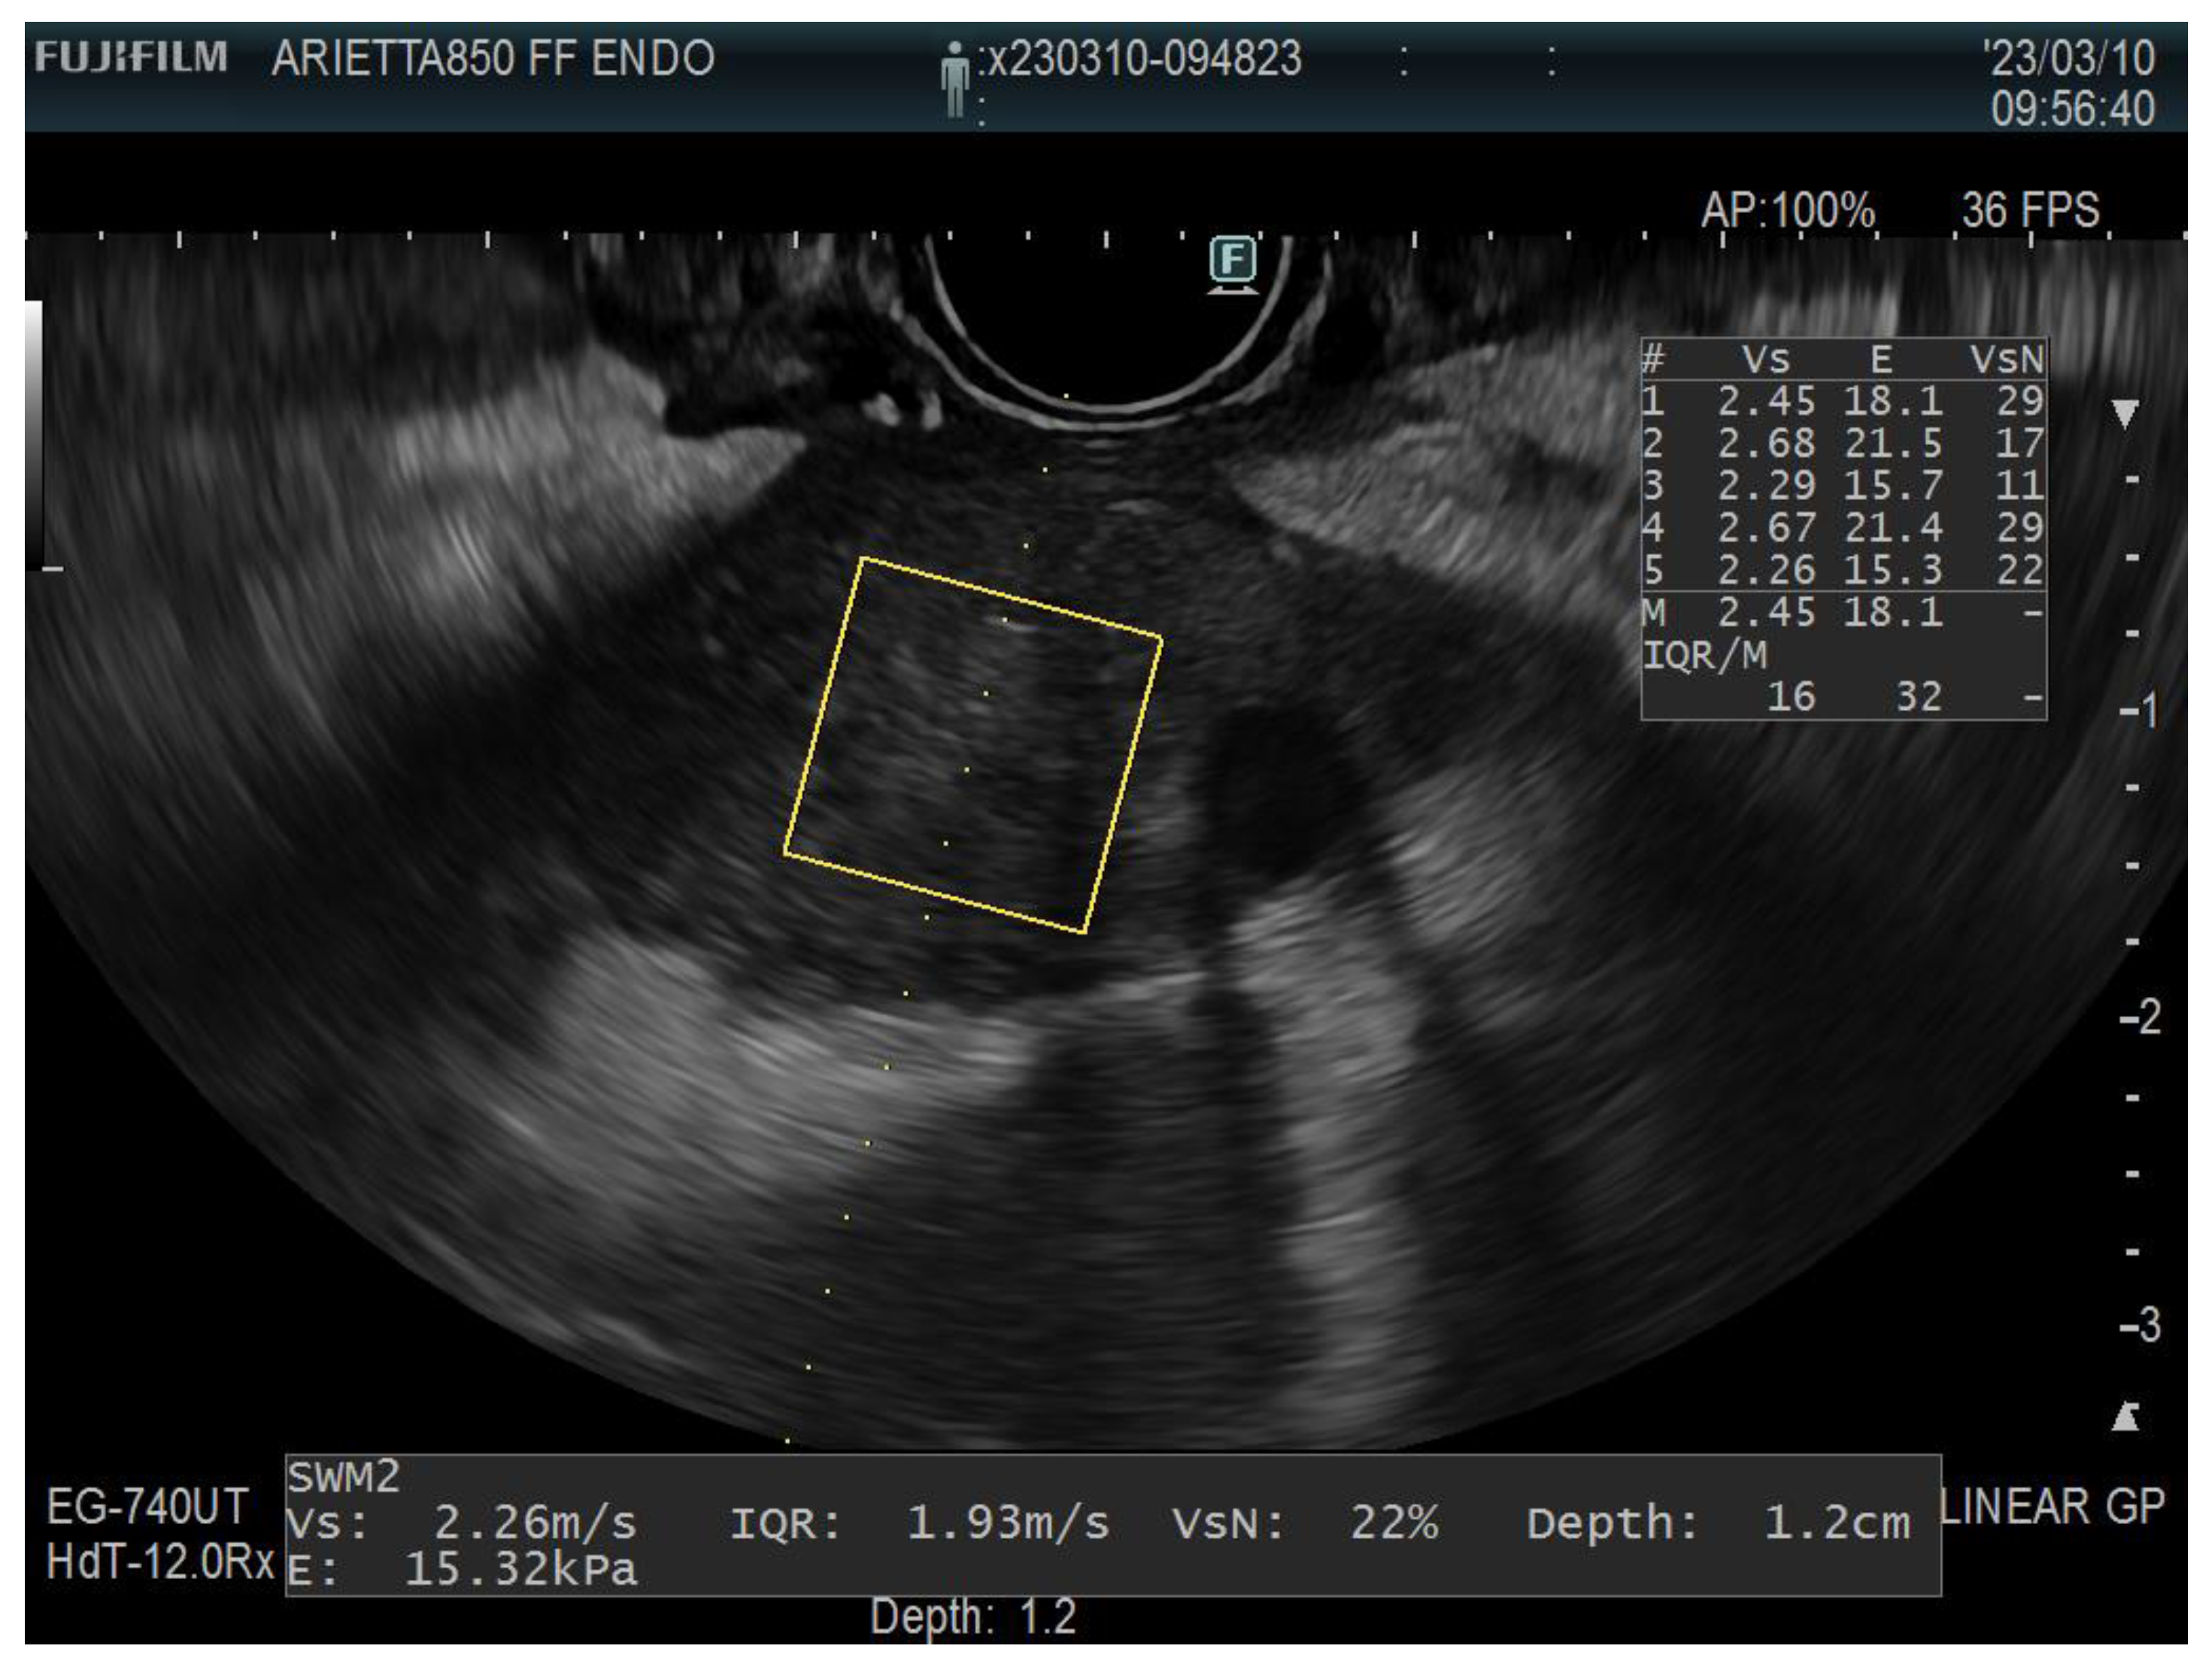

2.2. Shear Wave Elastography